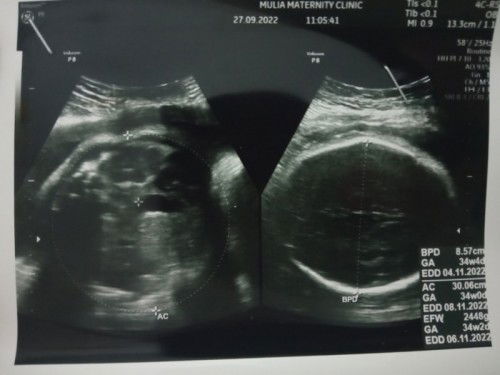

#bantusharing #serius nanya # Hasil usg 34 minggu bbj 2,4kg kata dokter normal, tadi waktu aku periksa ke bidan usia kandungan 36minggu bbj nya 3,8 dg tinngi fundus 36cm dan berat badan aku 72 tinggi aku 163cm,, benerbener stres bun pdhl selama ini aku jarang bgt bgt makan es bakso atau pun yg manis karna emang ga suka, apakah akurat ya bun perkiraan bidan karna aku suka makan malem karna emang lapar aku tife org yg jarang ngemil meskipun lg hamil#seriusnanya